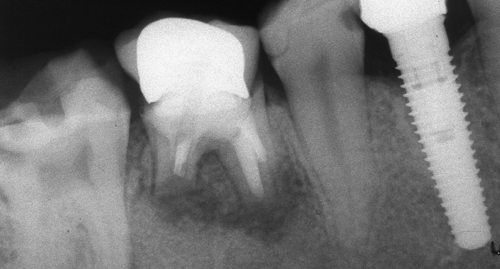

Оралната хирургия е дял от денталната медицина. Понятието орална хирургия е доста условно - с него се обозначават различни видове оперативни интервенции в областта на устната кухина, въпреки че дори и почистването на един кариес по своята същност представлява оперативна интервенция (некректомия); екстирпацията на един нерв от зъбен канал, почистването на зъбен камък, пиленето на зъб за корона и запълването на коренов канал също са оперативни интервенции, понякога технически доста сложни. Все пак всички тези манипулации са извън обема на оралната хирургия - тя включва екстракцията на ретинирани зъби, отстраняването на кисти от зъбен произход, на малки по обем доброкачествени тумори, и, разбира се, поставянето на зъбни импланти. Всички необходими манипулации за осъществяването на костна пластика при имплантатите също влизат в обема на оралната хирургия.